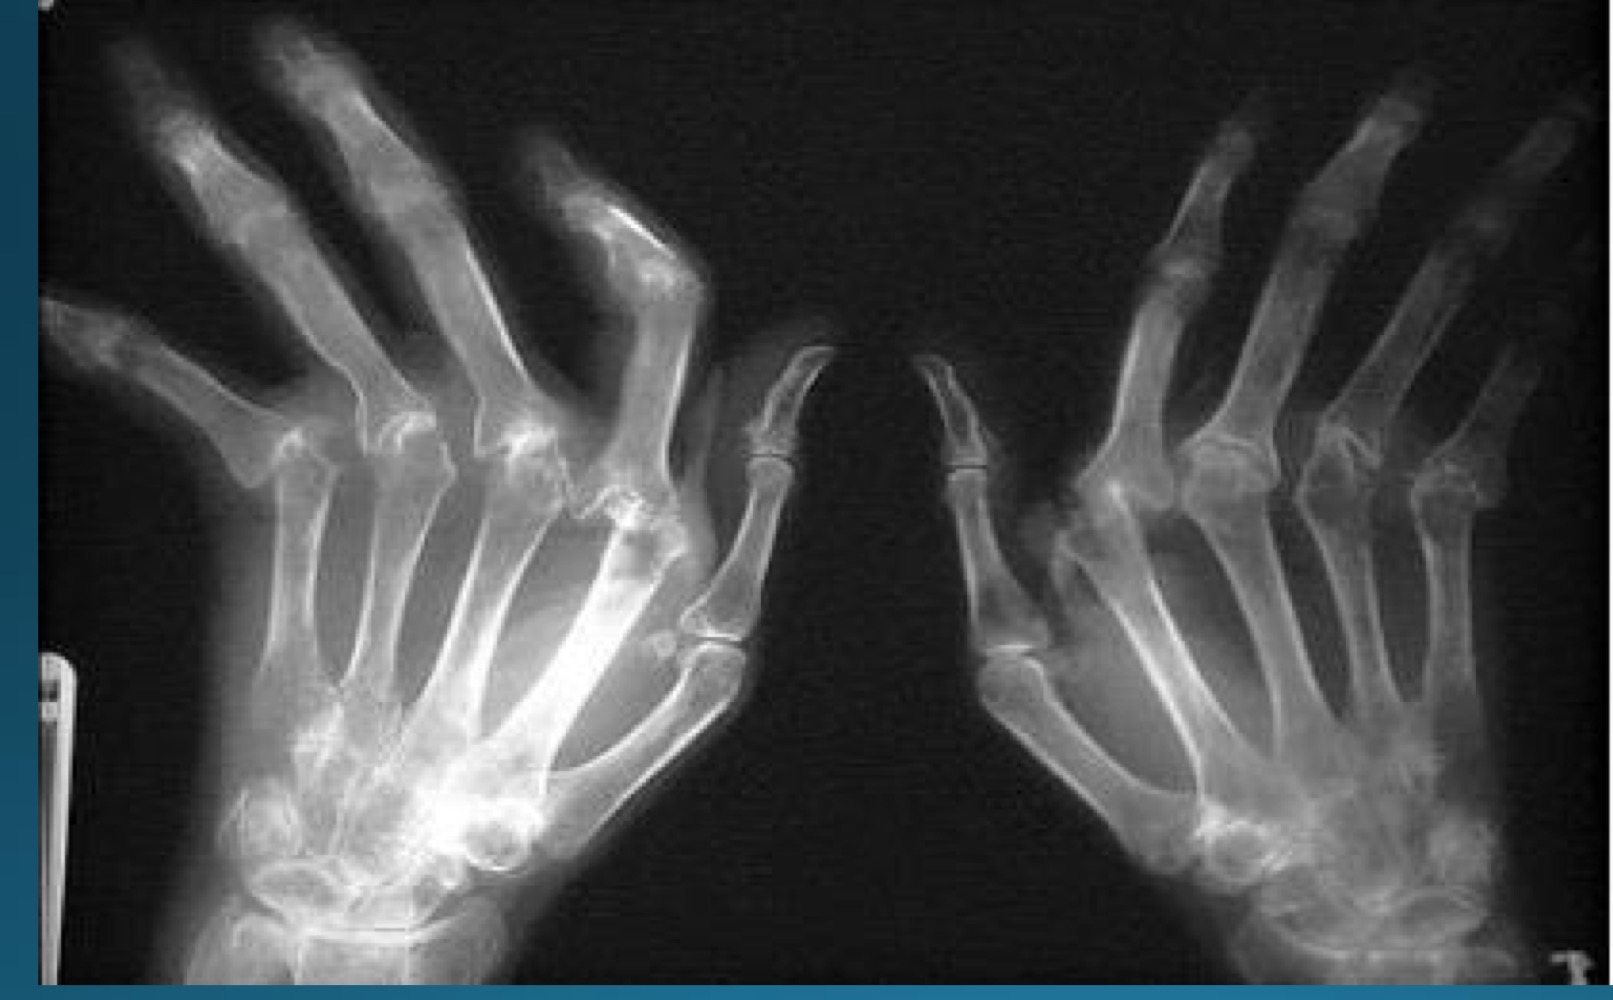

what is the diagnosis

RA

what is the diagnosis and major finding?

periarticular swelling